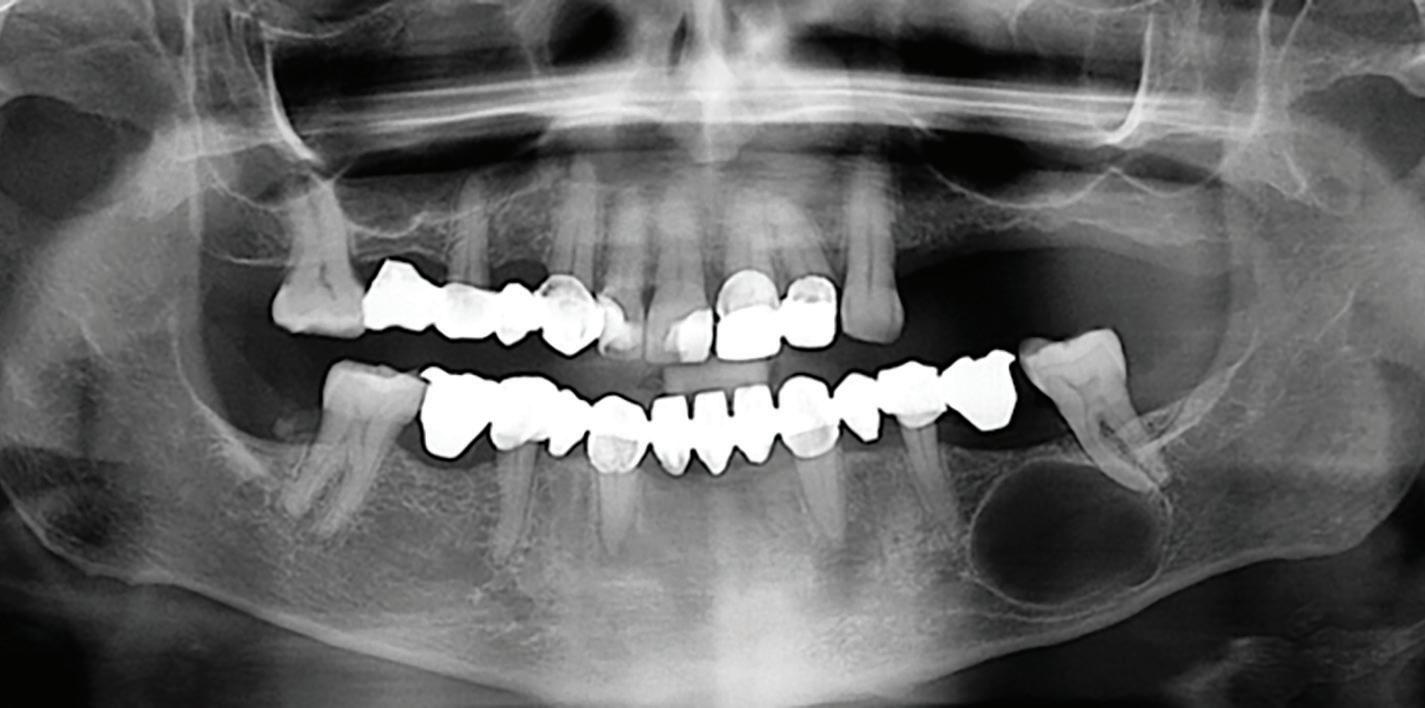

After tooth extraction and socket preservation, patients heal for at least 3 to 4 months. Once the healing process is complete, among the most important procedures for implant planning are cone beam computed tomographic (CBCT) and intraoral scans. The CBCT scan is a 3-dimensional (3D) radiograph that shows the patient’s bone in ways that cannot be seen on 2-dimensional images such as periapical, bitewing, or panoramic radiographs. The use of CBCT scans for implant cases is becoming common because of the important information provided, including bone height, bone width, and the location of arteries, veins, nerves, and other important anatomical features.2

In addition, CBCT images can be used to assess bone density. Bone density ranges from D1 to D4.3 The density is measured in a ratio of cortical-to-cancellous bone. Cortical bone, which makes

up the outer portion of the bone, is dense and has low vascularity. Cancellous bone, which makes up the inner portion of the bone, is not dense and has higher vascularity. D1 bone consists of a high percentage of highly dense cortical bone and minimal to no cancellous bone. D4 bone has a high percentage of low-density cancellous bone and little to no cortical bone. In bone that is more cortical and more dense, the clinician will generally make a larger osteotomy to reduce the stress put on the dense bone. In bone that is less dense and more trabecular, the clinician can make a more undersized osteotomy to ensure good primary stability of the implant. Depending on the type and density of bone found on the preoperative CBCT, the clinician can modify the implant placement technique to adjust for the findings. In my experience, the density of grafted sites is usually classified as D2, but this can vary depending on the type of graft used (Fig 1 and 2).

Fig 1. CBCT images confirm healing of the extraction site after grafting. Fig 2. An occlusal CBCT view reveals the density of the healed graft.